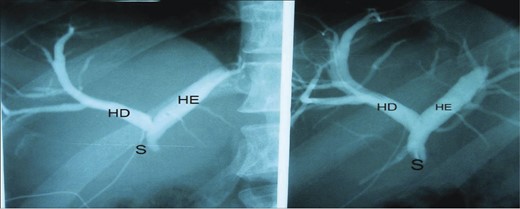

The patient was submitted to surgical intervention. Inspection showed a small fistula (probably the duct of Luschka [6]) in the gallbladder bed, the common hepatic duct was sectioned with loss of substance between segments, and the proximal and distal stumps were ligated with cotton suture. Next, catheterization of the fistula in the duct of the gallbladder bed was performed with a No. 4 Levine catheter. Cholangiography showed moderate dilatation of the intrahepatic bile duct and a sudden obstruction in the common hepatic duct 1 cm from the confluence of the hepatic ducts, corresponding to bile duct injury classified as Bismuth II (Fig. 1).

Right hepatic duct (RH), left hepatic duct (LH) and obstructed common hepatic duct (O).